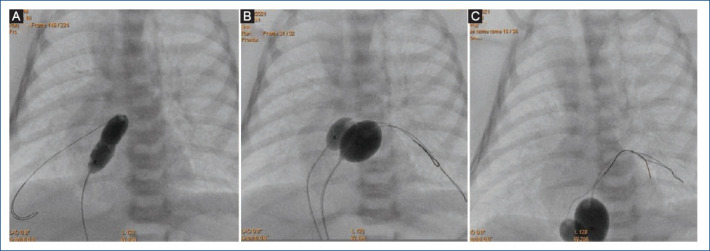

Objectives: Balloon atrial septostomy (BAS) is a palliative procedure mainly for newborns with transposition of the great arteries, currently, this procedure has a class IA recommendation. However, in some cases, this procedure does not achieve an adequate interatrial defect, due mainly to a thickened interatrial septum, this situation led to the development of various techniques to tackle this problem. Therefore, we made a modification to the original technique using two balloons simultaneously instead of one. The objective of this study is to analyze the results of this new modification to the traditional technique (with one balloon) as an alternative for cases with thickened interatrial septum.

Results: Six patients were identified (median age 35 days, median weight 3.4 kg, median size of atrial septal defect before procedure 2.6 mm). All patients underwent to this modification of the BAS with good results and without complications. The modification has some advantages: including to avoid the using of cutting devices or stent placement. In addition, we share the description of this new technique, titled: double "dynamic" BAS.

Conclusion: This brief evidence shown that this modification of de original technique is easy, safe, and cost-effective for cases with a thickened interatrial septum.